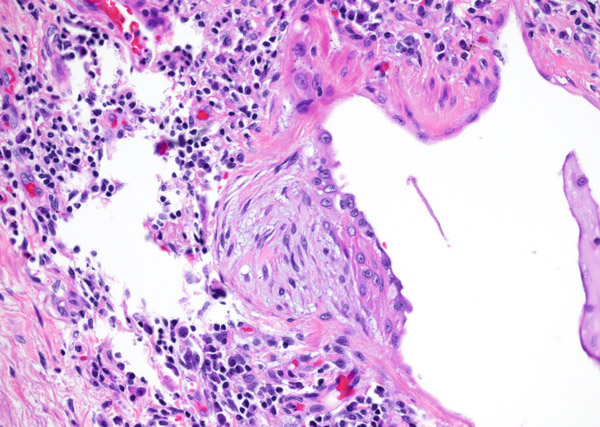

Clinical History: A 75-year-old man presented with increasing shortness of breath and cough. He had been complaining of worsening symptoms for the past year and a half and had been treated with multiple rounds of antibiotics for pneumonia which failed to improve his symptoms. Sections are shown from the right lower lobe (Figures 1-6).

Usual interstitial pneumonia (UIP) is a fibrosing interstitial pneumonia and is one of the more common interstitial lung disease diagnoses made by the surgical pathologist. It is an important diagnosis not to miss and also not to overcall as it has important clinical consequences (treatment with anti-fibrotics and possible lung transplantation after disease progression). UIP is the pathologic correlate to the clinical term idiopathic pulmonary fibrosis (IPF) and as its clinical moniker implies the cause of UIP/IPF is unknown. It is hypothesized that there is some form of ongoing damage occurring within the lungs to incite a fibrotic response. The fibrosis is more prominent peripherally and in the lower lobes. Histologic features required for diagnosis include temporal and spatial heterogeneity, fibroblastic foci, and honeycombing. Fibroblastic foci are located within the interstitium and most commonly at the border of the advancing fibrosis. They are composed of a proliferation of fibroblasts and their nuclei are usually arranged parallel to the interstitium. They form small outpouchings within the interstitium and can be appreciated on low power by their myxoid appearance (Figure 1). They should be distinguished from fibroblastic plugs which are seen in organizing pneumonia. Fibroblastic plugs look similar but are located within airspaces and not in the interstitium. While fibroblastic foci should be present in order to diagnose UIP (with rare exceptions), it is important to note that they are not specific for UIP and can be seen in other interstitial lung diseases. Honeycombing is another key feature for the diagnosis of UIP. It consists of architecturally distorted airways surrounded by fibrosis and often with inspissated secretions (Figures 2 and 3). In UIP, honeycombing is typically most prominent in the lower lobes and at the bases and less so in the upper lobes. UIP shows a distinctive appearance on lower power of normal-appearing lung juxtaposed with severely fibrotic lung (Figure 4). The fibrotic areas are often most extensive in subpleural parenchyma and along interlobular septa, leaving a donut of normal-appearing lung in the center (“spatial heterogeneity”) (Figures 5 and 6). Temporal heterogeneity refers to differing ages of fibrosis as well as the uninvolved lung as compared to heavily involved lung. A mild chronic inflammatory component is often seen in UIP but if the inflammation is severe and widespread other diagnoses should be considered.